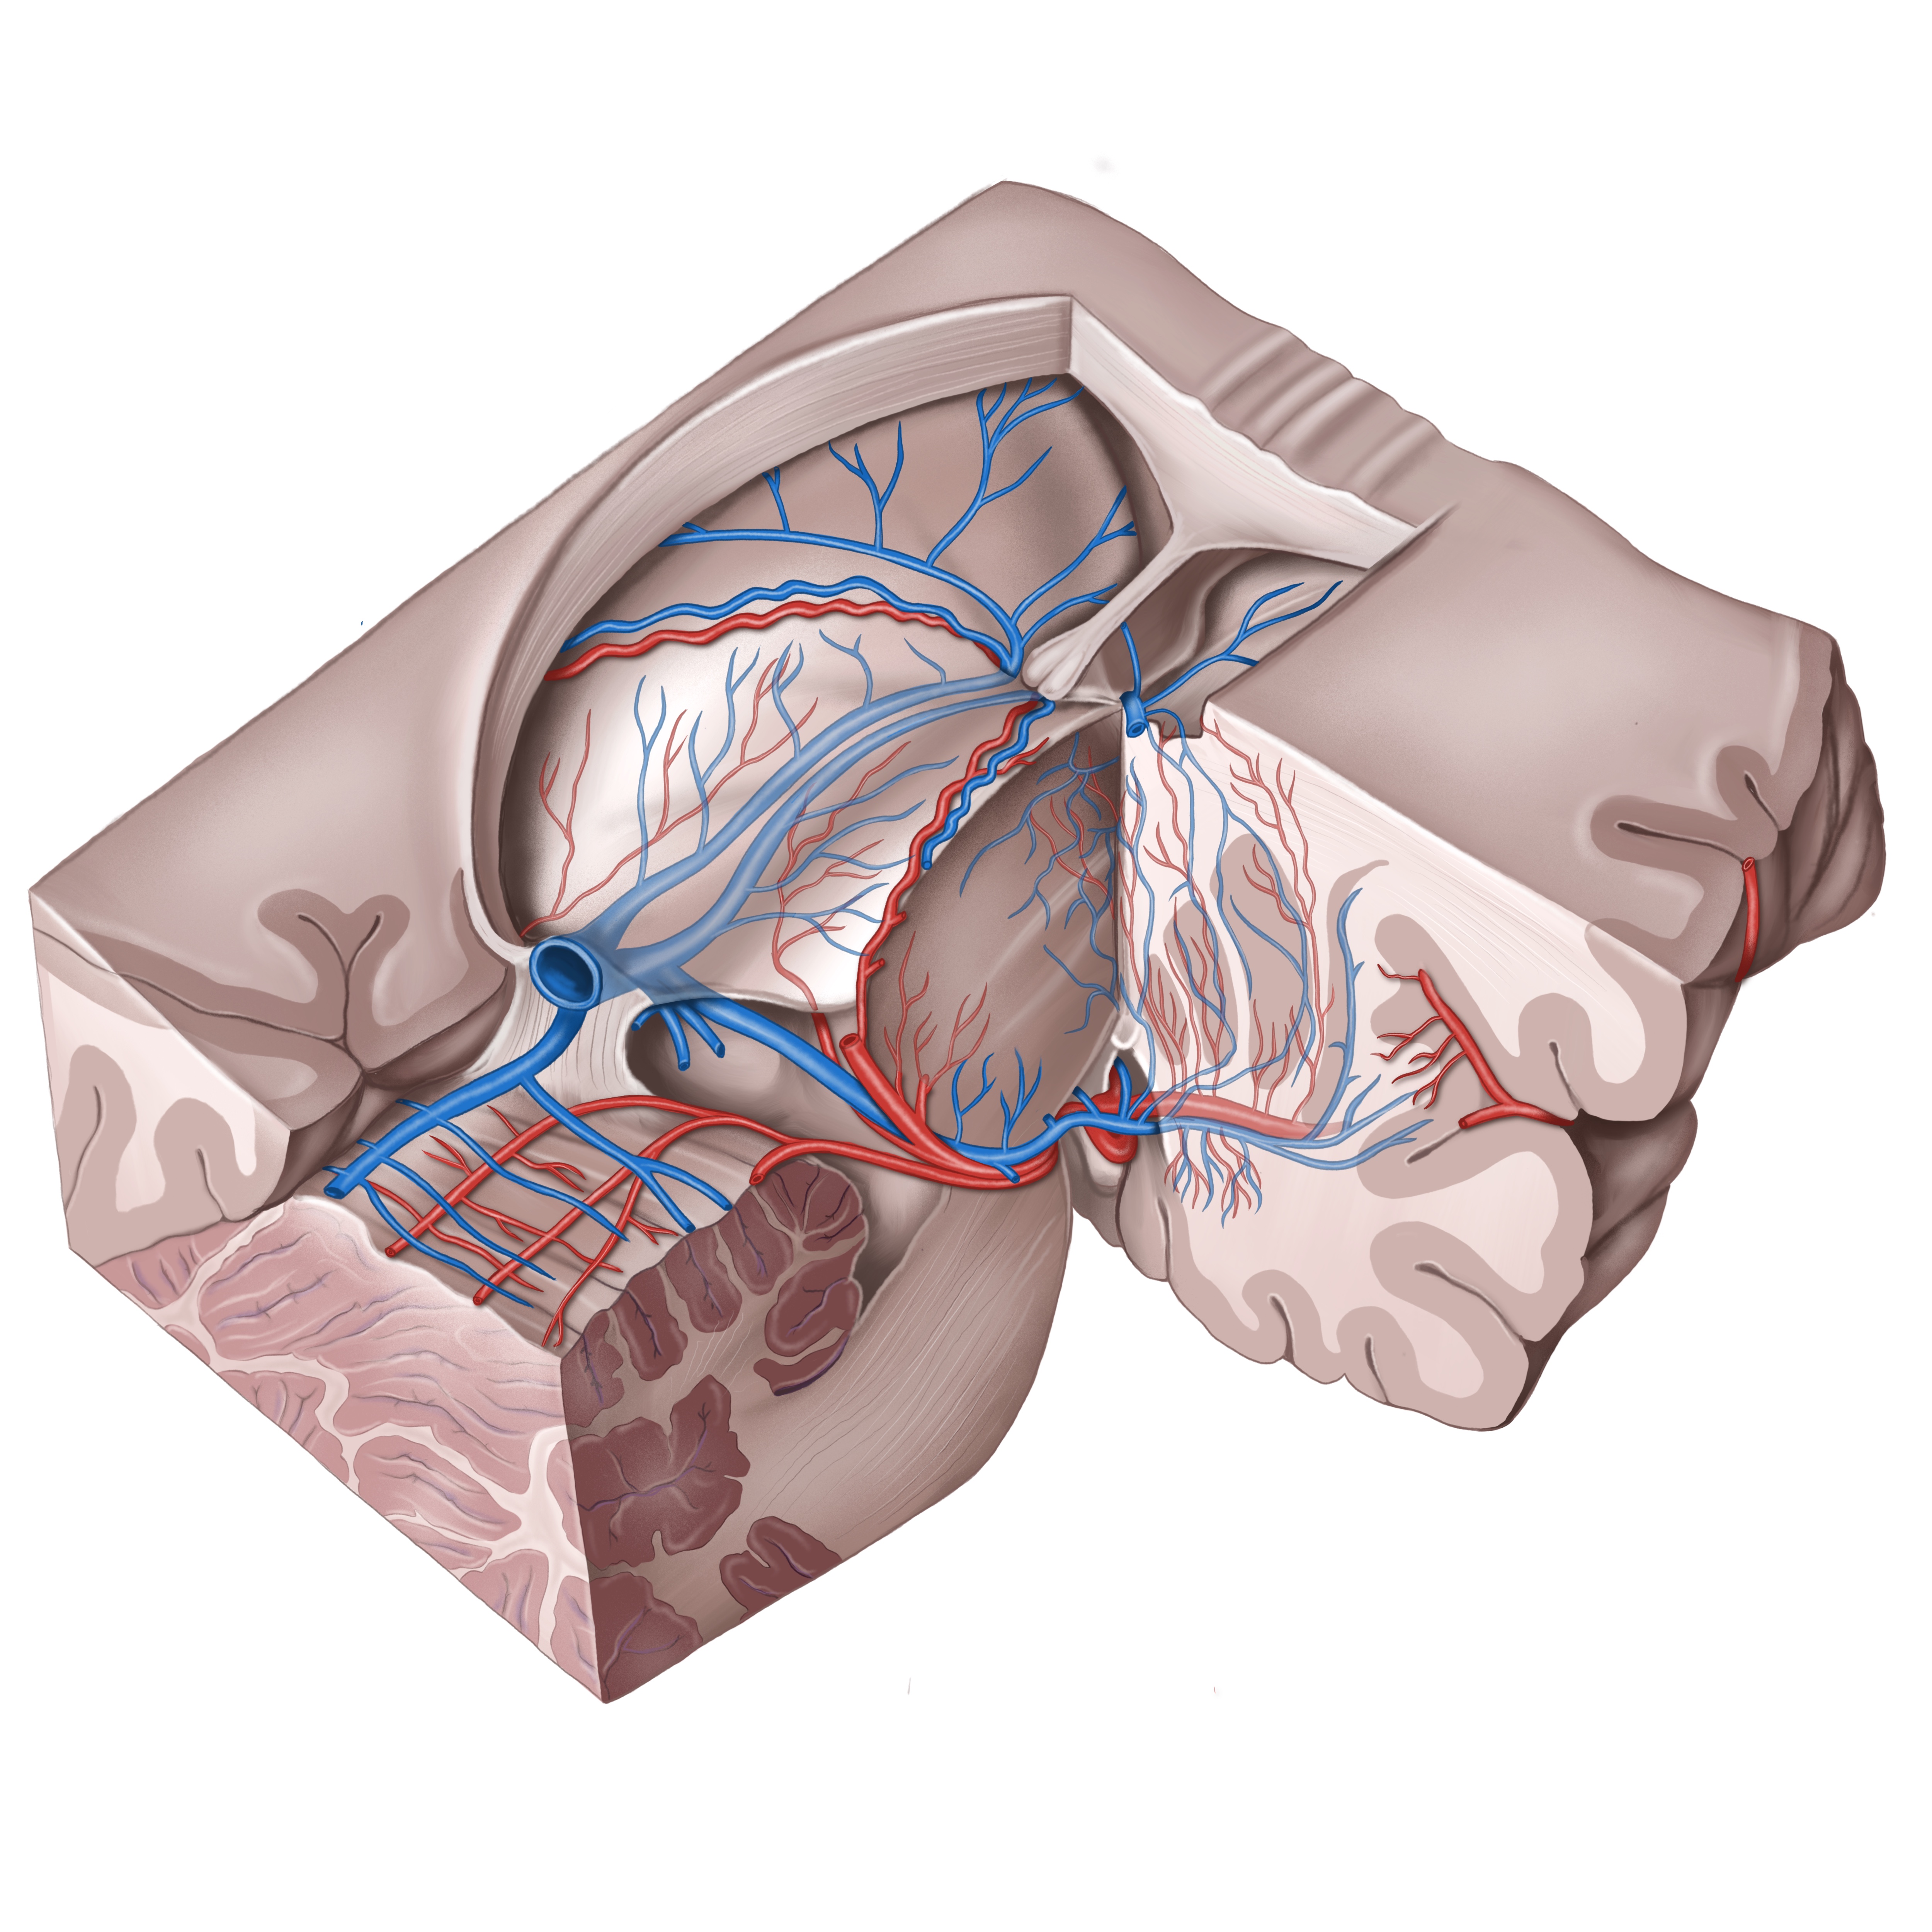

Анатомия внутренней яремной вены: КТ изображения